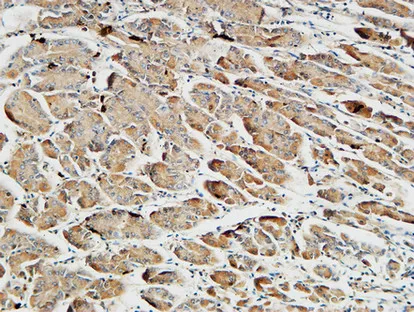

Somatostatin Rabbit Polyclonal Antibody

Cat: APRab18109